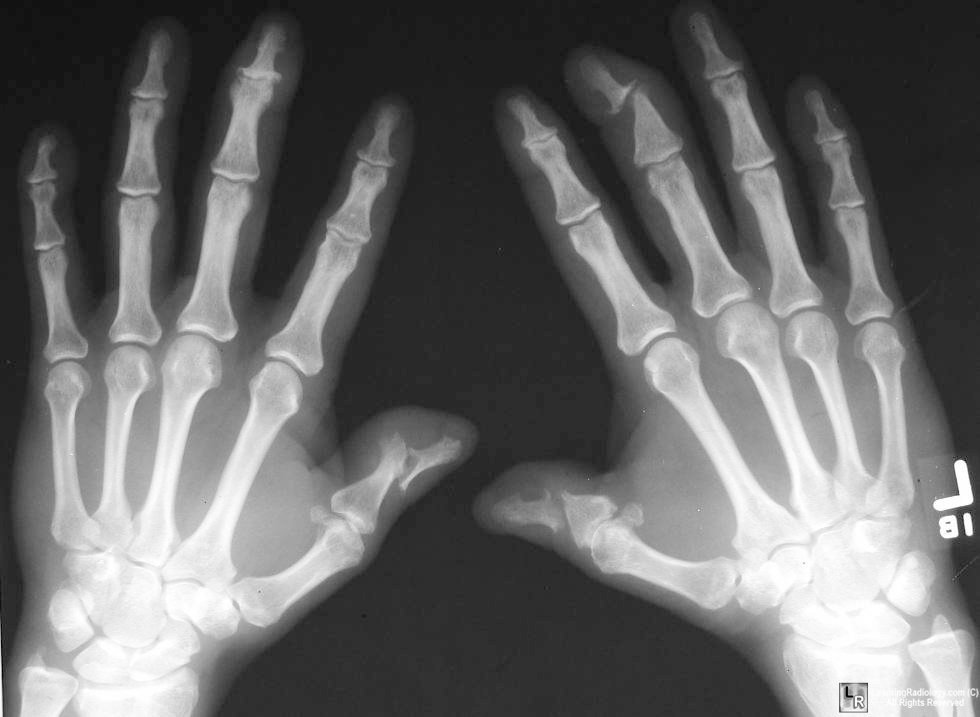

What type of arthritis?

Characteristics?

Erosive OA

old women

See Erosions–> Gull wing deformity

predominantly the IPs, (1st CMC cannot get erosive OA)